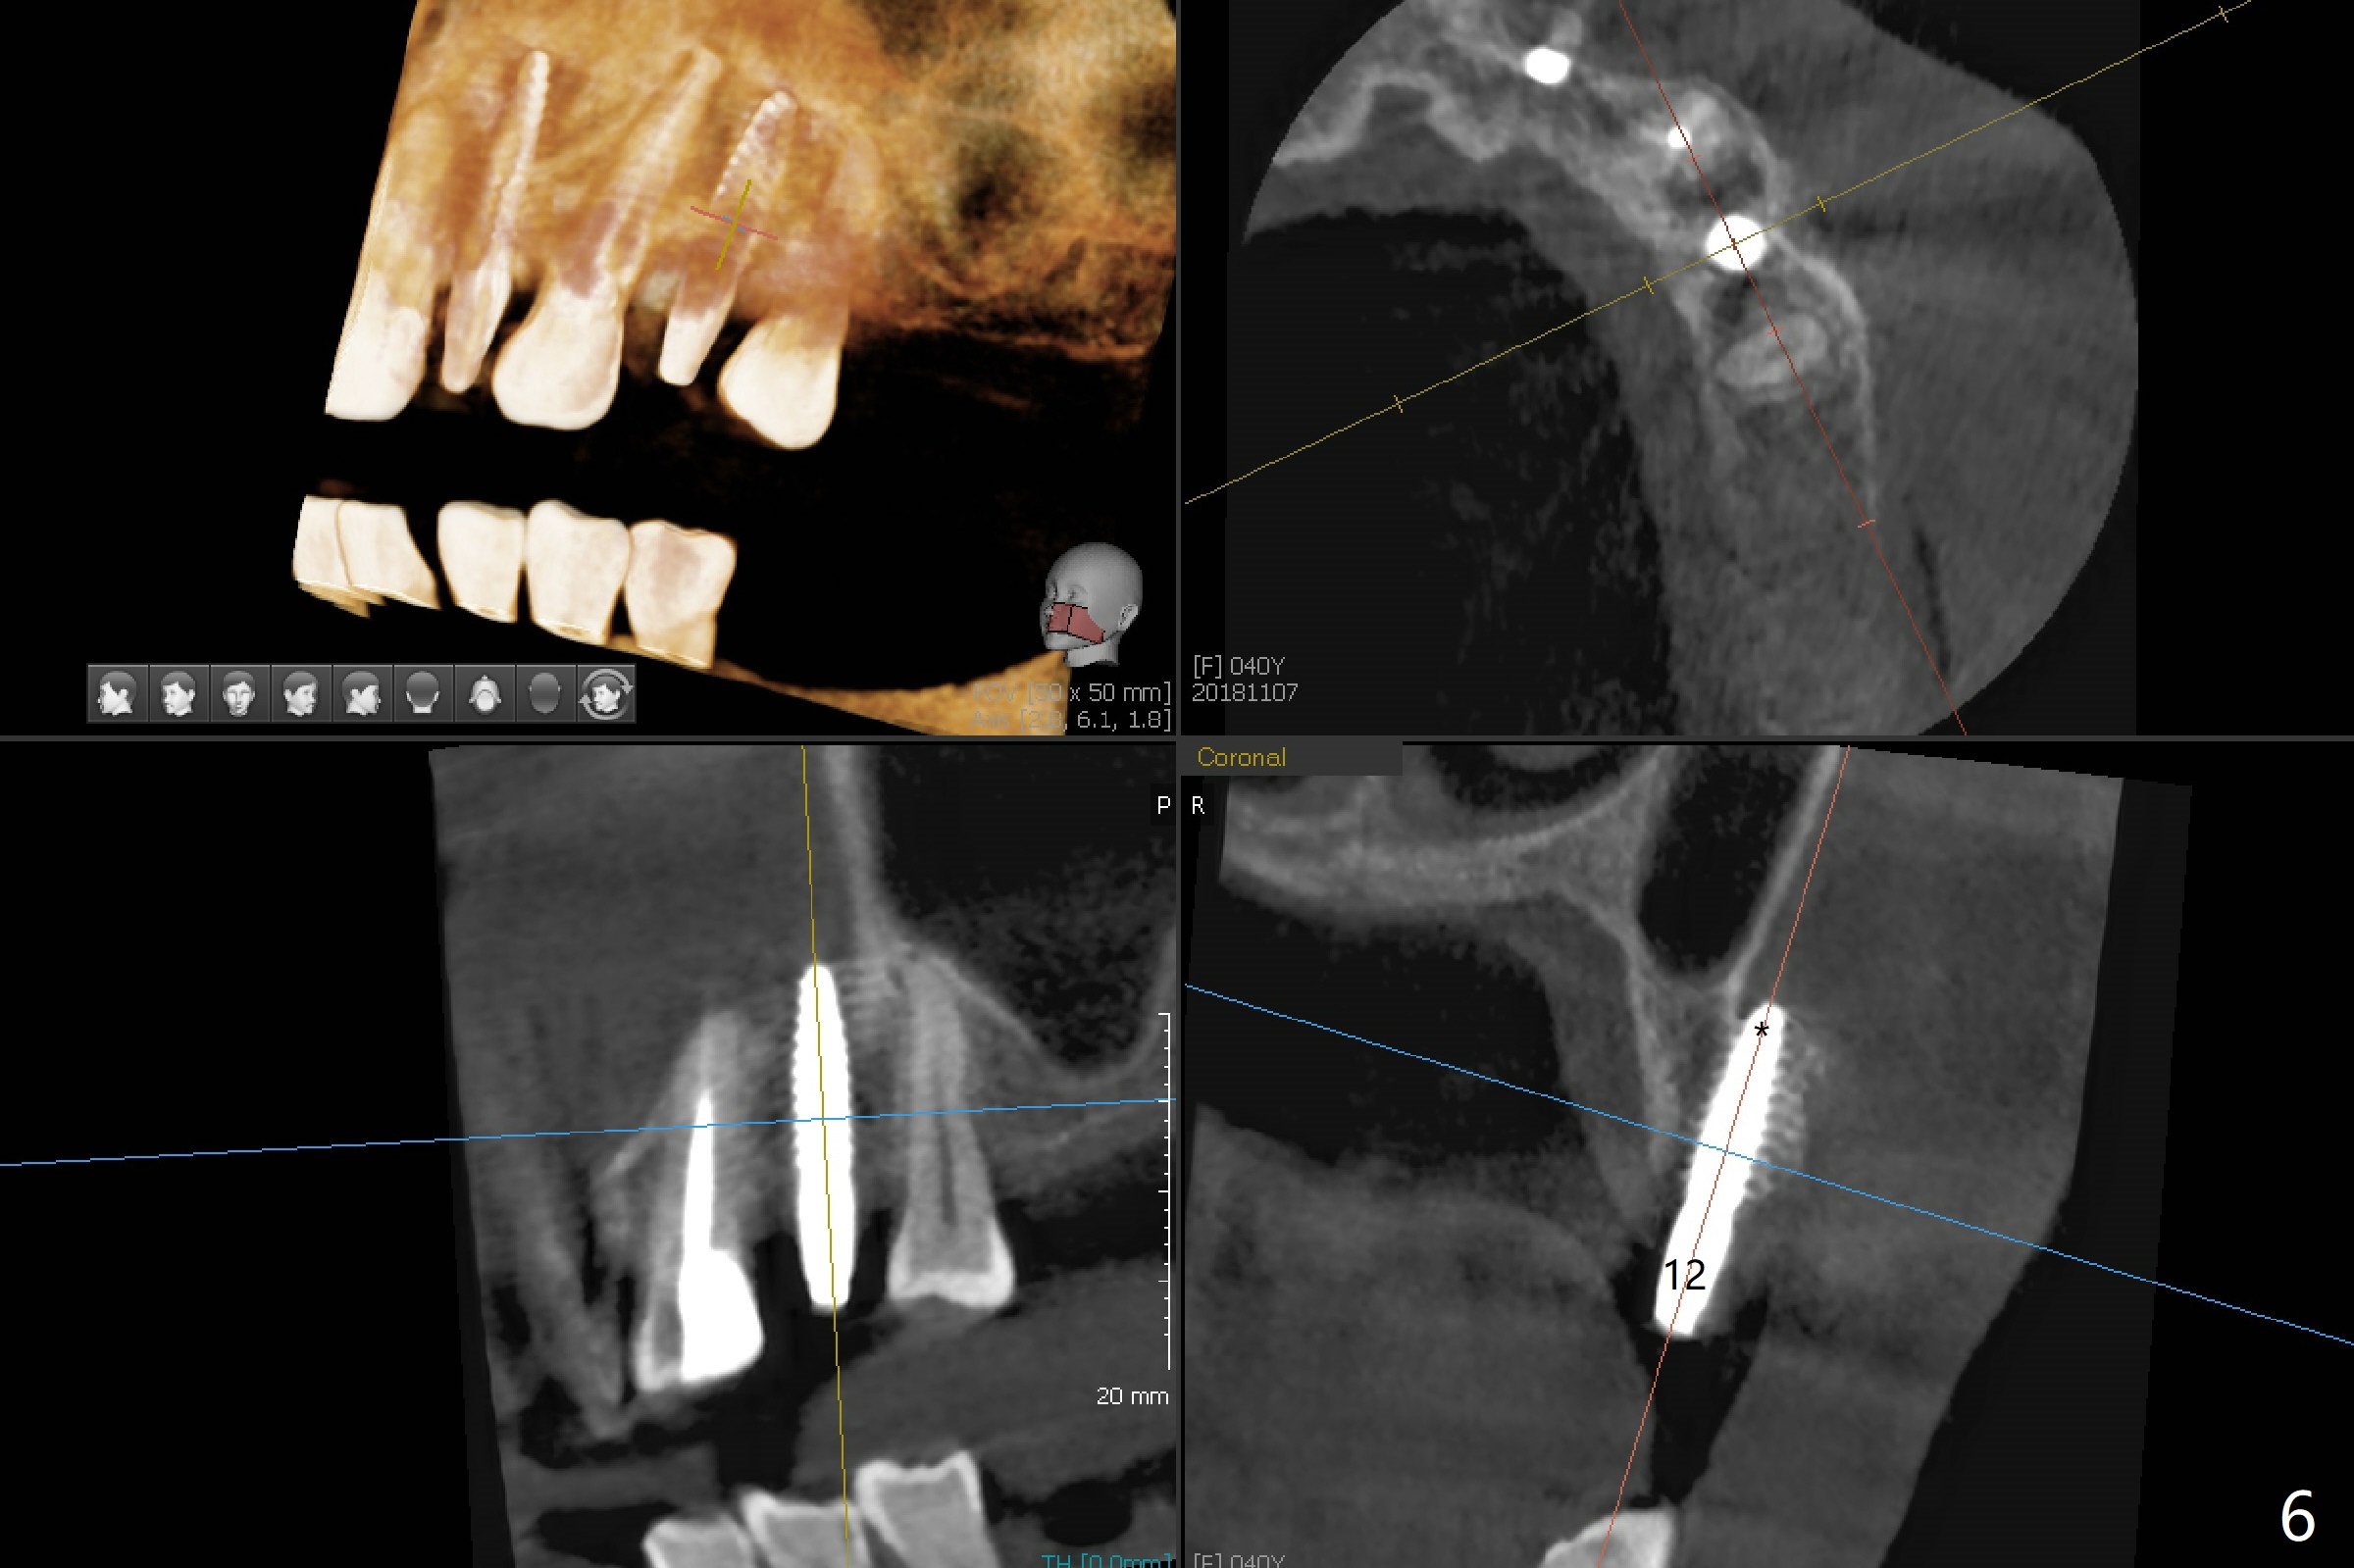

After removal of #10 sleeve and 3 spot adjustment, the guide is seated without satisfaction. When the guide is removed after pointed drill, the osteotomy seems distal (Fig.1). Incision is made with flap elevation for free hand osteotomy. A 1/1.6 mm bone expander is inserted after 1.2 mm drill, the trajectory appears to be right (Fig.2). As the osteotomy increases in diameter, the buccal plate feels to be vibratory. A 3.5x11.5 mm 1-piece implant placed initially is apparently away the sinus floor (Fig.3). Further placement (subcrestal, Fig.4) seems to be associated with more buccal plate perforation (Fig.6 *), which is repaired by bone graft. Since the implant at #10 appears to be doing okay 1.5 months postop (Fig.5), the implant at #12 is not removed immediately. A tunnel incision will be made for bone graft in the most apical concave areas (Fig.7). The osteotomy should have been made more palatal to reduce the chance of the buccal perforation. CBCT should have been taken while the 1/1.6 bone expander was in place.